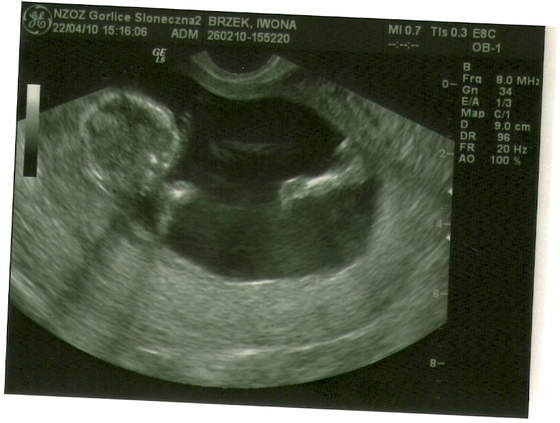

skanowanie0003.jpgskanowanie0004.jpgskanowanie0002.jpga to moja niunia:-)

no i oczywiscie wsio ok jest 2 raczki 2 noznki po 5 paluszkow:) 2 komory mozgowe serducho bije jest zoladek i pecherz moczowy czyli nerki pracuja NT-1.5 KOSC NOSOWA UWIDOCZNIONA:) NO I STRASZNIE LUBI ZAKLADAC NOGE NA NOGE...HMMM